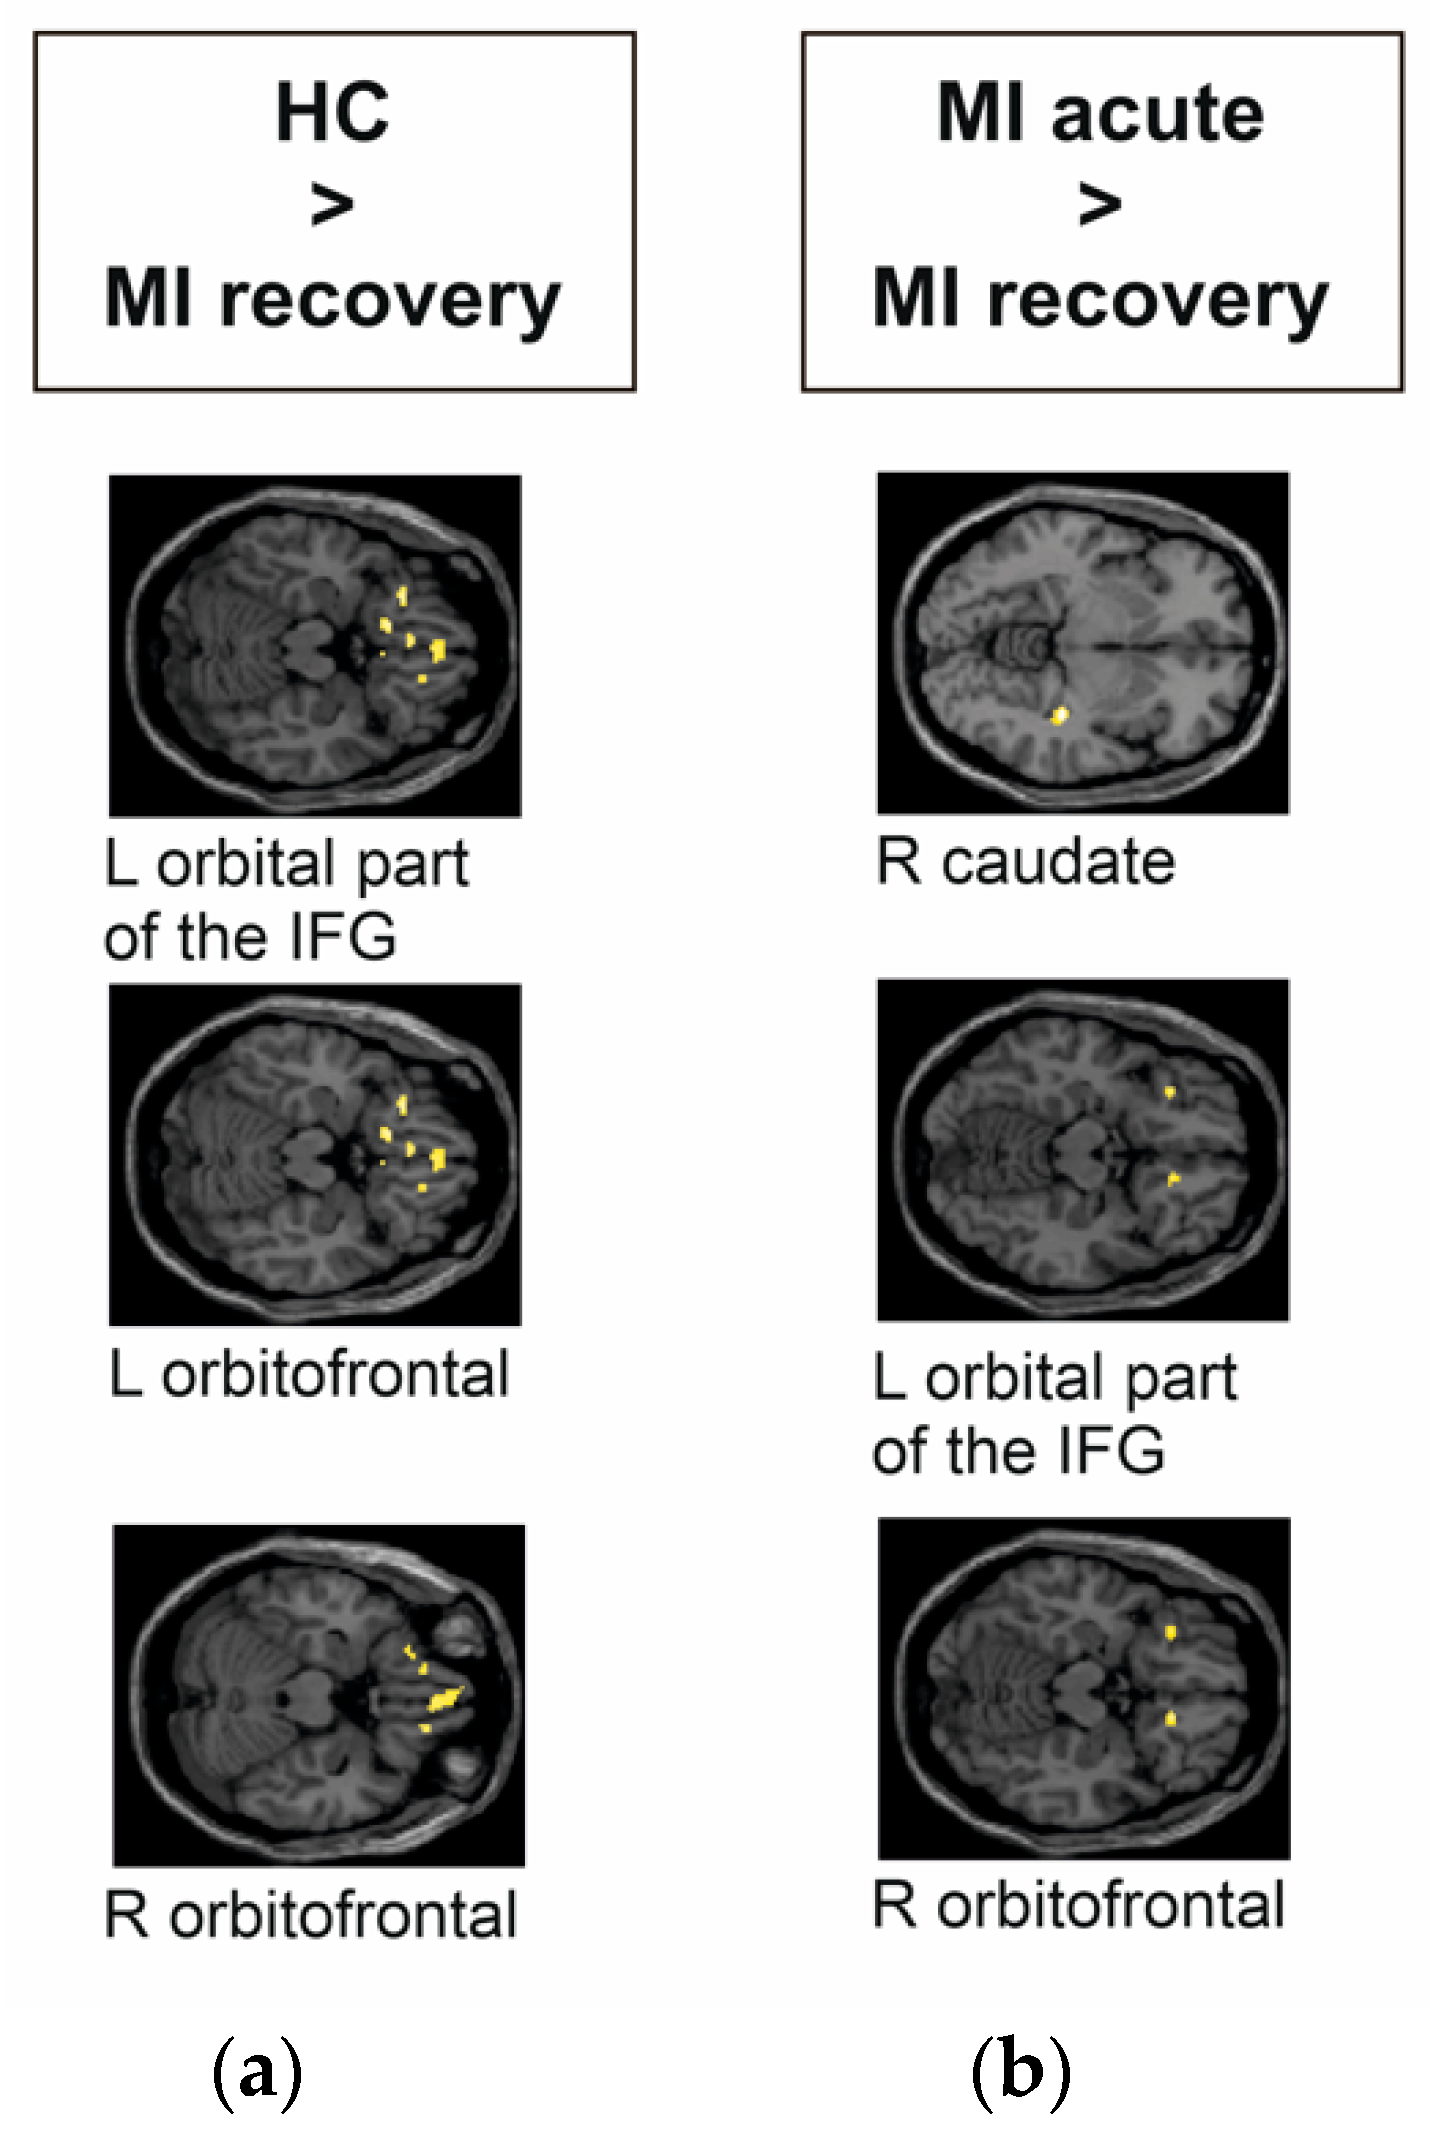

| Group Contrast | Number of Voxels | MNI Coordinate | Region | T Value | p Value |

|---|---|---|---|---|---|

| HC > MI recovery phase | 122 | 2, 44, −22 | R orbitofrontal | 3.82 | 0.000 |

| 55 | −26, 28, −18 | L orbital part of the IFG | 4.21 | 0.000 | |

| 33 | −26, 28, −18 | L orbitofrontal | 4.22 | 0.000 | |

| MI acute phase > MI recovery phase | 45 | 34, −30, −7 | R caudate | 5.50 | 0.000 |

| 45 | −30, 28, −14 | L orbital part of the IFG | 4.53 | 0.000 | |

| 29 | 14, 28, −16 | R orbitofrontal | 4.78 | 0.000 |